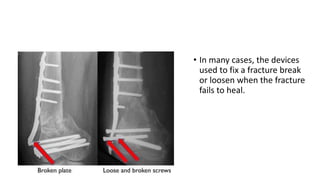

• In many cases, the devices

used to fix a fracture break

or loosen when the fracture

fails to heal.

3) nonunions :

• Up to 19%, most commonly in metaphyseal area, with articular

portion healed (comminution, bone loss and open fractures more

likely in metaphysis)

• Decreasing with less invasive techniques

• Treatment with revision ORIF and autograft indicated

• Consider changing fixation technique to improve biomechanics

• In manycases, the devices used to fix a fracture break or loosen when the fracture fails to heal.

3) nonunions : •Up to 19%, most commonly in metaphyseal area, with articular portion healed (comminution, bone loss and open fractures more likely in metaphysis) • Decreasing with less invasive techniques • Treatment with revision ORIF and autograft indicated • Consider changing fixation technique to improve biomechanics